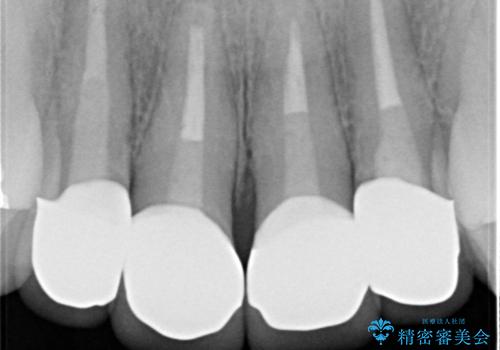

- 「黒ずんで、見栄えの悪い前歯をきれいにしたい。」と、前歯のセラミック治療を希望され来院されました。

全て根管治療のすでになされている歯の変色で、オールセラミッククラウンによる審美性の改善を計画します。